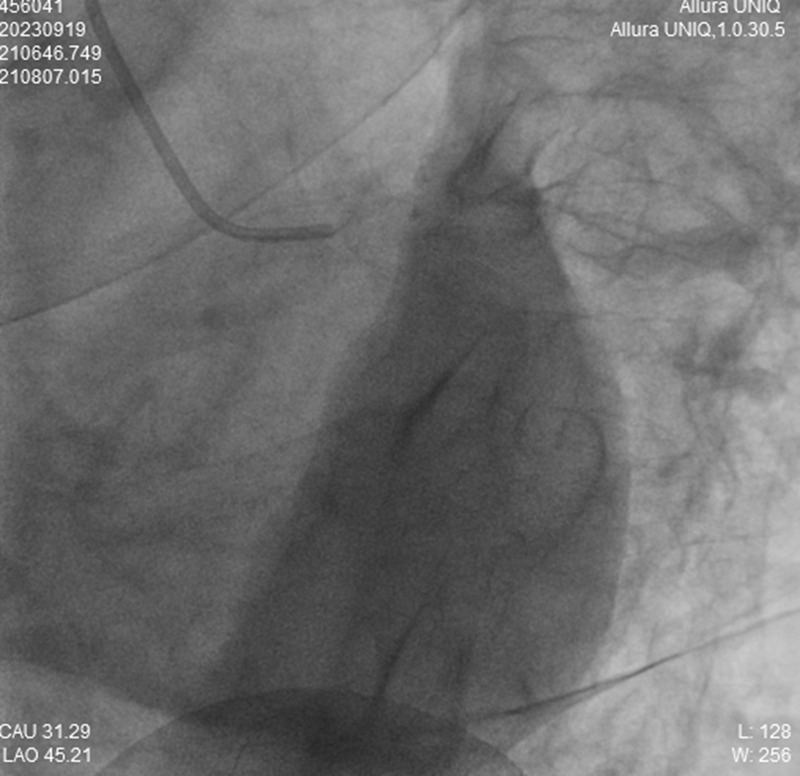

定位、消毒、穿刺、泥鳅导丝送入……危急时刻,救心团队以最快的速度为吴大叔实行冠脉造影。果不其然,结果显示确实是最凶险的心梗,且是“无保护左主干完全闭塞”!左主干血流全部中断,无其它侧支循环保护供血。

【左主干造影,完全闭塞】